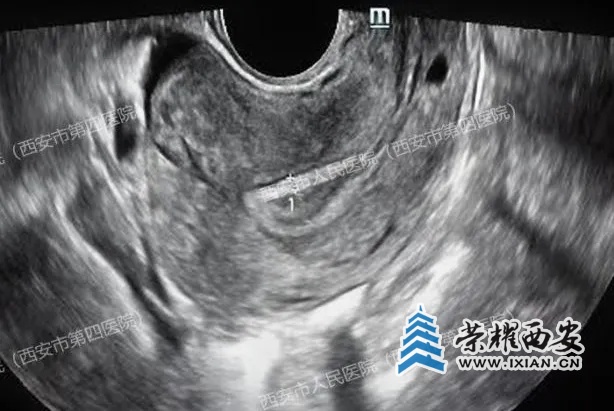

(上图腔内超声显示宫腔内未见孕囊,下图显示右侧卵巢小囊肿)

医生觉得疑惑,耐心安抚患者的同时又全面细致的沿子宫周围及上方扩展了扫查范围,当扫查到肝脏时,顿时惊呆了......胎儿竟然长在了肝脏上!!!

(肝右叶有一个47x35mm的囊实性占位,附件区包块影像显示为卵巢巧克力样囊肿,并非妊娠囊)